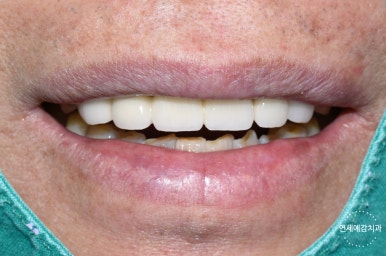

이렇게 전 후 사진비교해보니

브릿지를 하고 훨씬 나아졌습니다.

환자분께서 나머지 다른 앞니들은 충치도 있고 예뻐지려고 라미네이트를 할 예정이라고 하셨기 때문에

조금더 본인 치아색보다 하얀 색으로 진행하였습니다.

임플란트 할때보다 빠르게 진행되었고

뼈이식도 안해도 되었으며

환자분도 굉장히 만족하셔서 수정없이 진행하였고

다른 충치 앞니도 꼭 저희 치과에서 라미네이트 하겠다고 하셨습니다.